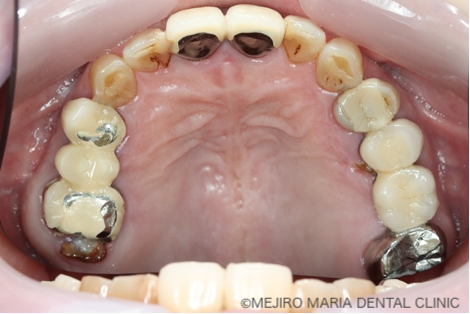

治療前の状態・主訴

患者様は、長年にわたり臼歯部(奥歯)の噛み合わせの調子が悪いことと、食事の際に痛みを感じることを主訴に来院されました。前歯部から口腔内を確認すると大きなトラブルは確認できませんが、レントゲン撮影と口腔内診査を行うと、多数の臼歯部の歯牙(歯)が歯根破折により抜歯を余儀なくされる状況でした。

まずは、歯周組織検査を含めた口腔内診査、レントゲン写真の撮影により、保存できる歯牙と、抜歯をせざるを得ない歯牙などを選定しました。

今回の症例では、歯根破折していた5本の歯牙(下の写真・赤矢印)に対して、抜歯を提案した。また、診断用WaxUp(ワックスアップ)を行ったところ左下のブリッジ(青丸)と右下(青矢印)の噛み合わせ平面が乱れており、咬合に負担をかけていることが予想されました。そのため、最終的にそれらの不調和を改善し、適切な噛み合わせにすることをゴールとして治療を開始しました。